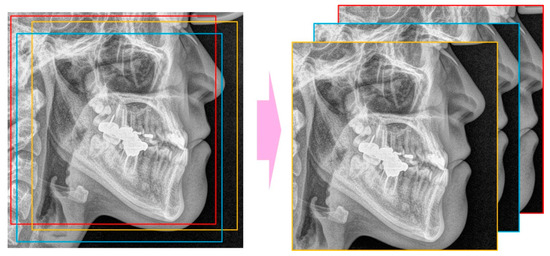

The landmarks of the patients’ cephalometric radiographs were automatically detected with a software program using a gradient boosting algorithm (WebCeph, AssembleCircle, Seoul, Korea). WebCeph has been used for landmark detection in several studies [24,25]. The minimum box, including all the landmarks, was selected with an external margin of 5% and the lower part of the box was selected by square cropping. The image was resized to 256 × 256 pixels.

The CNN models used were ResNet-18, 34, 50, and 101 (Figure 2) [26]. The number was determined by the difference in the depth of the blocks that constitute the model. As ResNet models use an image of 224 × 224 pixels as the default input image, the input image was selected by randomly cropping the 256 × 256 image (Figure 3).

Figure 3.

Random cropping to get 224 × 224 images from 256 × 256 image.